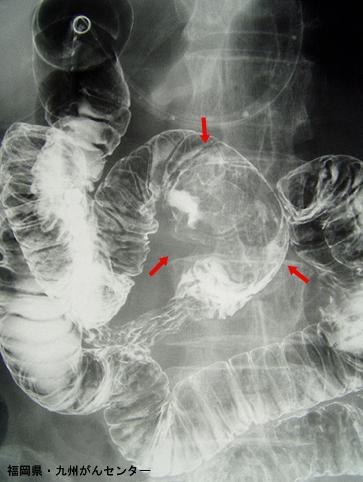

症例提示(所在地,施設名等): 福岡県・ 九州がんセンター

疾患(病理主体)の分類悪性非上皮性腫瘍/平滑筋肉腫(含GIST)

部位(臓器別)十二指腸/上行脚

検査方法X-P

病変の最大径(ミリ)40以上